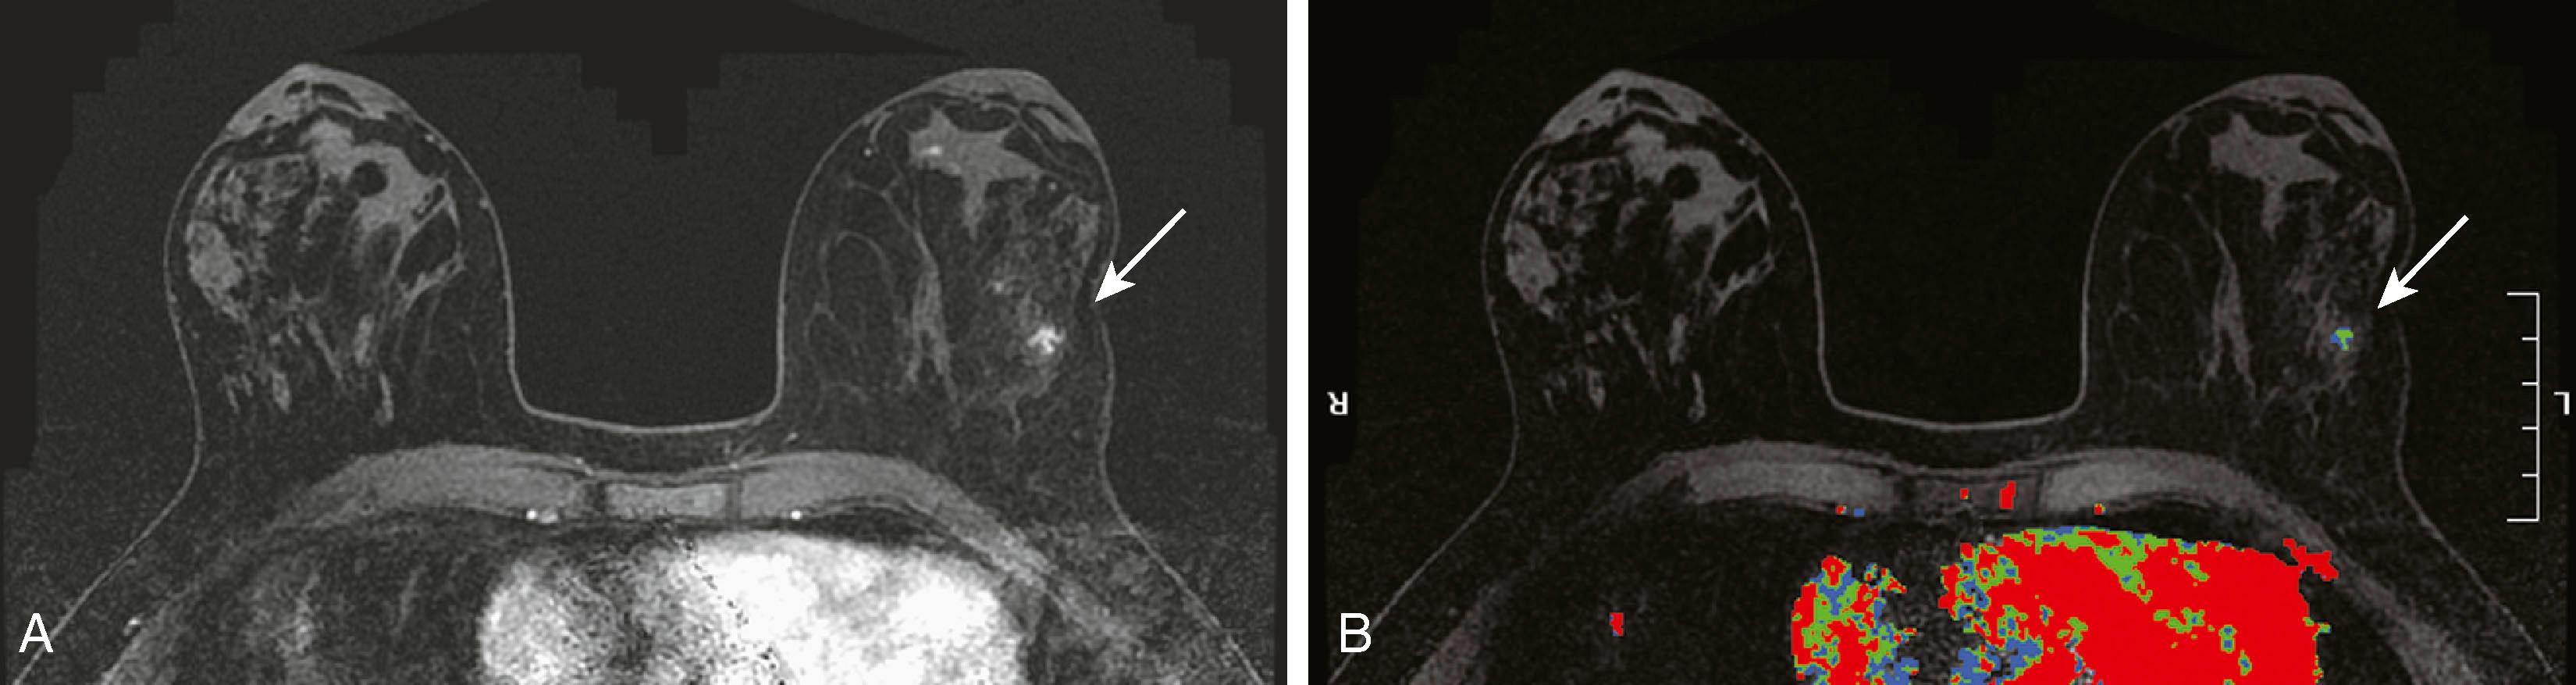

MRI detects breast disease by virtue of its ability, after the administration of a gadolinium-based contrast agent, to demonstrate neovascularity in tumors. Breast tumors, especially malignant ones, have more and larger vessels with higher permeability to contrast. In addition, there is an increase in the interstitial extravascular space of tumors. Typically, breast cancers enhance rapidly (within the first minute or so of contrast administration) followed by rapid washout over 10 to 15 minutes ( Fig. 8.22 ). This is the typical “kinetic signature” of cancer but, unfortunately, it is not absolute. There are a few cancers that demonstrate delayed enhancement with progressive accumulation of contrast and benign lesions, such as fibroadenomas, typically cellular, that enhance rapidly and wash out quickly ( Fig. 8.23 ). Therefore, when MRI-visible lesions are characterized, both the kinetic profile and the morphology must be considered. The morphological features that we have come to associate with breast cancer by most imaging techniques are indistinct borders, spiculation, and irregularity of shape.

Fig. 8.22, ( A and B ) Two examples of malignant lesions (arrows) , colored red by computer-aided detection (CAD). ( C ) The curve shows the typical “kinetic signature” of cancer, which is quick enhancement, followed by rapid washout. ( D ) Magnetic resonance imaging with CAD demonstrates a fibroadenoma within the right breast (arrow) , colored blue by CAD. ( E ) The washout curve for this fibroadenoma shows persistent accumulation of contrast.

Fig. 8.23, ( A ) Maximal intensity projection with computer-aided detection demonstrates a carcinoma within the right breast (solid arrow) showing a heterogeneous kinetic pattern of red, green, and blue, which is actually most typical for carcinoma. The left breast (open arrow) demonstrates a lesion showing benign washout; however, it is a carcinoma. ( B ) Although the kinetic profile is benign, the morphology of this lesion was malignant (arrow) . ( C ) Large invasive ductal carcinoma demonstrates a heterogeneous kinetic pattern (arrow) . ( D ) Carcinoma demonstrates a ring of predominantly blue enhancement (arrow) . Ring enhancement, however, is a malignant morphological feature.

Protocols to image breast cancer can vary, but the basic technique of breast MRI is to scan both breasts rapidly over time before and after the administration of an intravenous gadolinium contrast agent. Scanning is usually performed in the axial plane, but in some institutions, the sagittal plane is preferred. Because these scans result in very large data sets (a typical study will commonly include well over 1,000 images), computer algorithms that simplify viewing are helpful. The software that displays the kinetic features of the breast is referred to as CAD software. CAD assigns a color map to areas of blood flow, which is color coded depending on the speed with which the contrast exits the lesion. To demonstrate this, the breasts must be scanned multiple times in rapid succession (called multiphasic imaging ) over a short period, typically 10 to 12 minutes. Newer protocols are evaluating the efficacy of shortening the exam time by limiting the number of post contrast series obtained. If the contrast exits the lesion quickly, it is called a washout pattern and is usually colored red. This is most typical of malignant lesions and benign or malignant lymph nodes. If the contrast stays at the same concentration throughout the scan, it is called a plateau pattern and is often colored green. This pattern is indeterminate for malignancy. If the contrast enters the lesion and the concentration of contrast continues to increase, it is characterized as a persistent pattern and is typically colored blue. This pattern is most commonly seen with benign lesions such as fibroadenomas and other fibrocystic conditions.